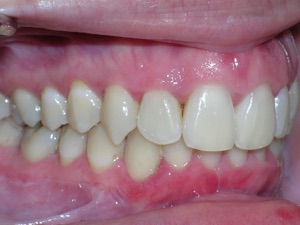

This case was of a young lady who desperately wanted Invisalign, but had been told it was not possible. There was not one, but two teeth that had come in toward the roof of the mouth.

Here are some progress photos.

Needless to say, we were both quite happy with the outcome. Using elastics we were able to push back the back teeth and create space for the two teeth stuck behind.